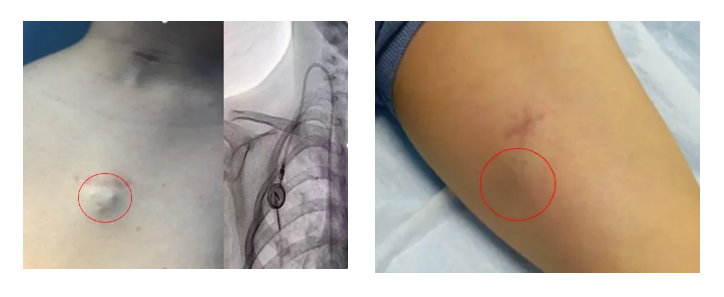

輸液港,即完全植入式輸液港(PORT),是一種可完全植入皮下并長(zhǎng)期留存體內(nèi)的輸液裝置,主要由注射座(又稱港體)和硅膠導(dǎo)管兩部分組成。注射座被埋植于胸部皮下,導(dǎo)管則連接到上腔靜脈,形成一個(gè)閉合的靜脈輸液系統(tǒng)。其常見(jiàn)類型有手臂輸液港與胸壁輸液港。

這一裝置在醫(yī)學(xué)界得到了廣泛應(yīng)用,尤其對(duì)于需要長(zhǎng)期或重復(fù)給藥的患者,如腫瘤患者化療藥物的輸注中,具有顯著優(yōu)勢(shì)。